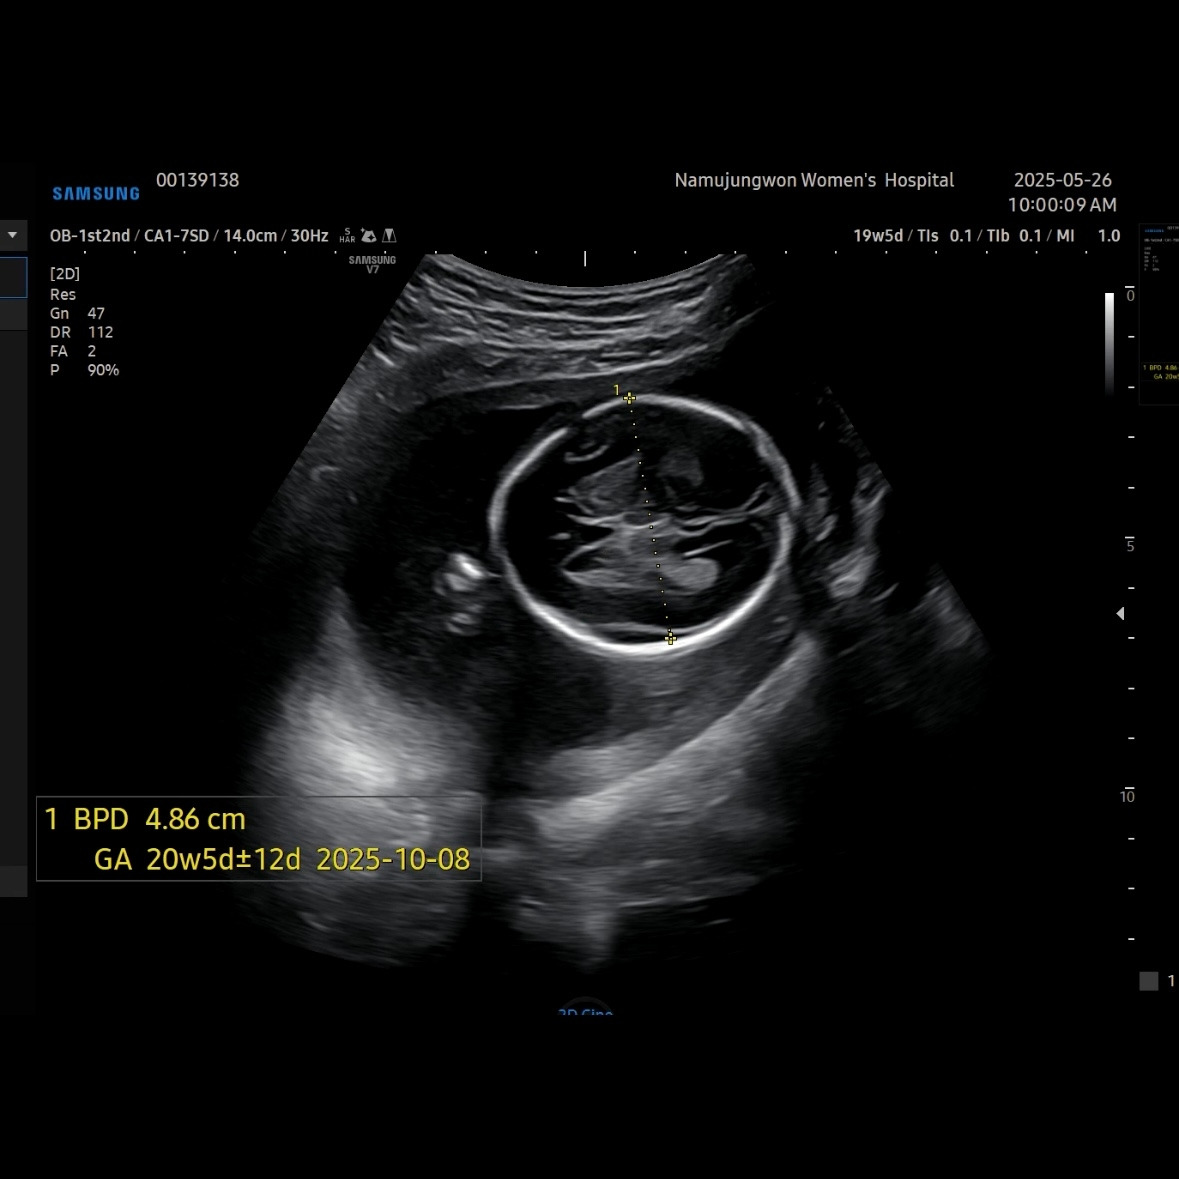

유민이 19주 5일 차에 보러 간 초음파

초음파를 보면 머리둘레, 배둘레, 허벅지 뼈길이를 꼭 재보는 데 유민이는 갈 때마다 1주 정도씩 평균보다 크게 측정된다. 1-2주 크기차이는 의미 없다고 괜찮다고 했다.